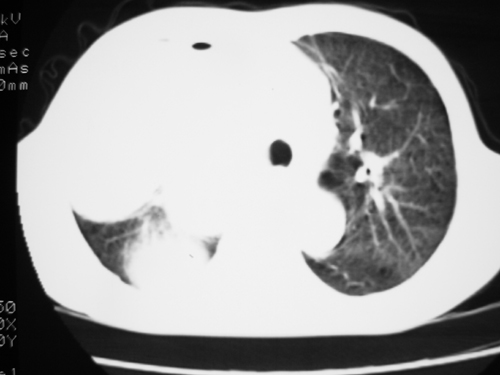

以下是引用yangyudong333在2008-4-29 5:46:00的发言:[br]1左上叶结节呈分叶状,边缘毛刺,考虑肺癌并纵隔淋巴结转移可能性大,结核待排,[br] [br]2右侧多发包裹性胸腔积液